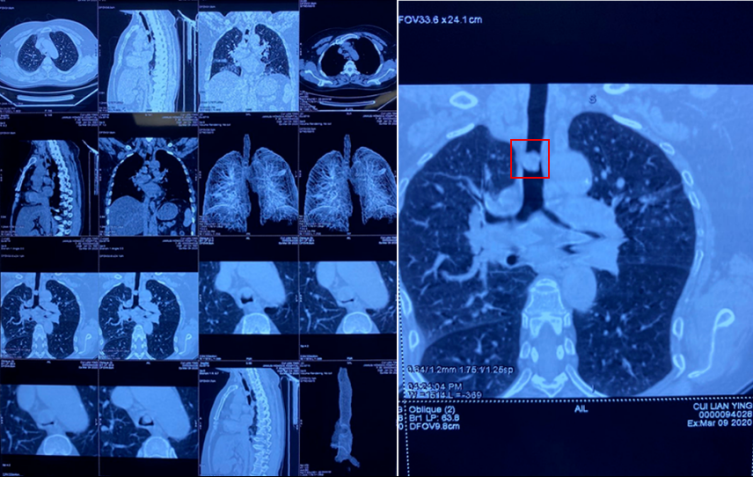

患者崔某,女,59歲,長期因胸悶氣短,呼吸困難4個月左右,多次輾轉(zhuǎn)于省內(nèi)各大醫(yī)院就診,因腫瘤位置特殊隱蔽少見,長期造成漏診誤診,總是以肺氣腫,支氣管炎接受治療,病情逐漸加重。尤其是近一個月,病人呼吸困難持續(xù)加重,端坐呼吸,日夜不能平臥,口唇紫紺,生命危在旦夕。經(jīng)人介紹來到了佳木斯大學(xué)宏大醫(yī)院胸外科就診,入院后胸部CT檢查發(fā)現(xiàn)主氣管腫瘤,阻塞氣管腔85%以上,病人出現(xiàn)窒息,隨時可能呼吸障礙死亡。

由于病人氣道巨大腫瘤阻塞,呼吸困難,吸氧緩解效果不良,只能依賴呼吸興奮劑等藥物緩解。術(shù)前胸外科手術(shù)團(tuán)隊(duì)聯(lián)合麻醉科左會明主任、手術(shù)室孫蘭英主任以及相關(guān)科室,詳細(xì)制定手術(shù)方案和應(yīng)急預(yù)案,決定采取超細(xì)氣管插管,解決手術(shù)麻醉通氣問題,打破常規(guī)采取雙麻醉機(jī)和雙通氣途徑,確保手術(shù)麻醉安全。術(shù)式?jīng)Q定為主氣管腫瘤切除氣道吻合成形重建術(shù)。對于手術(shù)風(fēng)險(xiǎn),病人及家屬對佳木斯大學(xué)宏大醫(yī)院及手術(shù)支持團(tuán)隊(duì)給予了充分的信任,并以生命相依托,相信手術(shù)定會成功。帶著病人及家屬的重托,手術(shù)團(tuán)隊(duì)經(jīng)過近4個小時努力,成功實(shí)施開胸手術(shù)切除胸段主氣管腫瘤,腫瘤大2.8*1.6*1.5CM,幾乎完全阻塞氣道。術(shù)中病理診斷為少見的氣管惡性腫瘤——惡性淋巴瘤。氣管I期吻合成功,術(shù)后無漏氣及出血。術(shù)中曾經(jīng)歷了驚心動魄的30秒低氧血癥期,心跳近乎停止,經(jīng)搶救轉(zhuǎn)危為安。